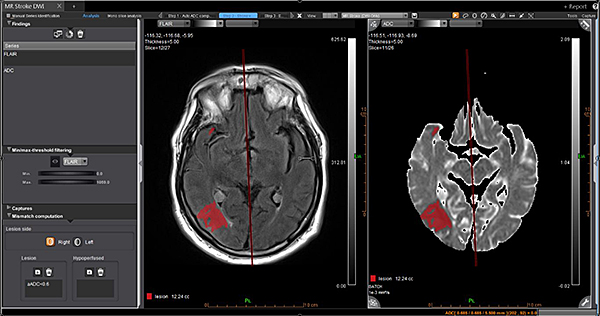

Дослідження інсульту MR Acute Care Stroke.

Незалежно від важкості невідкладного стану, ці додатки надають радіологам прямий доступ до звіту про інсульт в найкоротші терміни. Ці додатки включають інформацію про кровотік за допомогою унікальних динамічних порогових карт перфузії для візуальної оцінки гіпоперфузованих ділянок та використання методу Байєса для зменшення дози контрасту наполовину для перфузійного дослідження мозку.